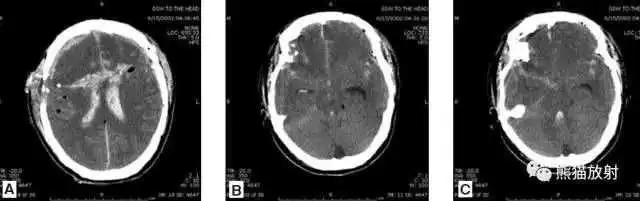

动脉瘤破裂导致蛛网膜下腔出血、

脑室积血、非交通性脑积水。

与外伤性蛛网膜下腔出血不同,动脉瘤破裂导致的SAH常不累及大脑凸面,而位于基底池附近。脑动脉瘤常位于鞍上池的Willis环血管。

A:四脑室积血;

B:中脑导水管、环池、右侧侧脑室颞角积血,前交通动脉处(动脉瘤好发位置)出血密度较高;

C:三脑室积血;

D-F:侧脑室积血,蛛网膜下腔出血(血液代替了脑脊液)。